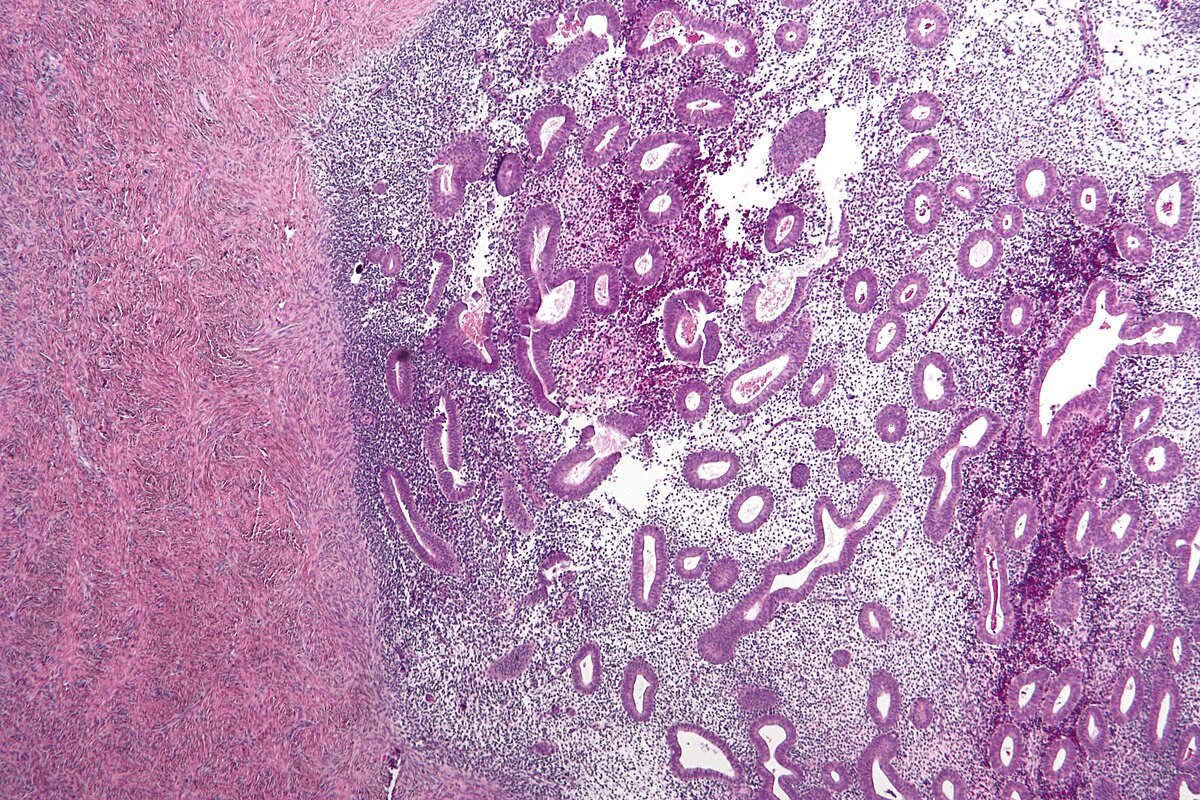

How is bladder cancer diagnosed?

Diagnosing bladder cancer often involves imaging tests, cystoscopy, and biopsy. The choice depends on the patient’s risk, symptoms, and disease extent.

Is a bladder biopsy necessary for diagnosing bladder cancer?

Yes, a bladder biopsy is usually needed to confirm bladder cancer. It takes a tissue sample from the bladder lining for cancer cell checks.